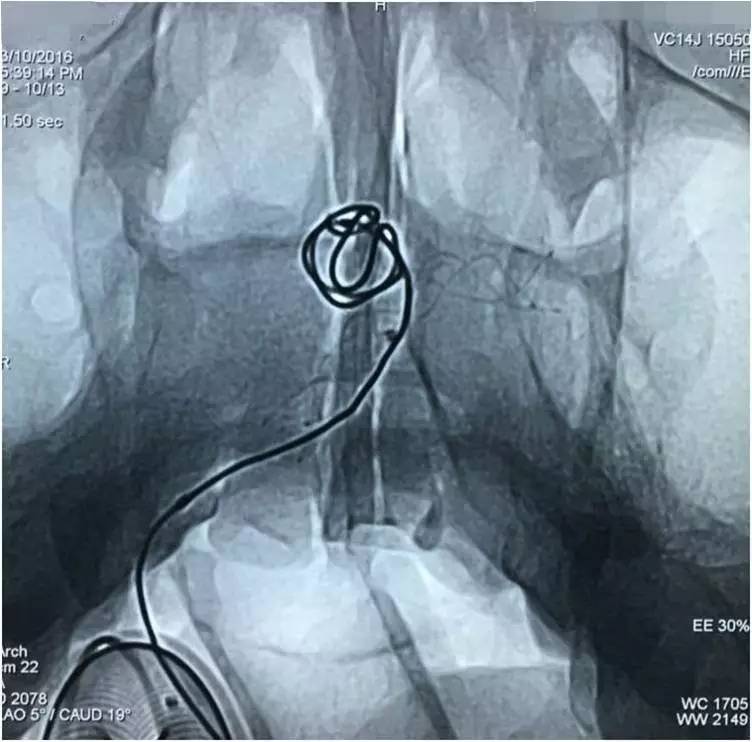

造影剂到底是从哪里漏进子瘤的呢?已经填塞到这种程度了,大造影是定位不了漏洞了,那就微量造影找吧!既然微导管从瘤腔的左后部填塞没达到消灭子瘤的目的,那么,反其道而行之,毅然撤出微导管,从支架网眼穿入瘤腔的右前部,看看漏洞是不是在此处?

▼影像资料

▼微量造影侧位显示子瘤显影。

▼空白路图填圈,惊喜地发现圈进入子瘤了,这是侧位空白路图。